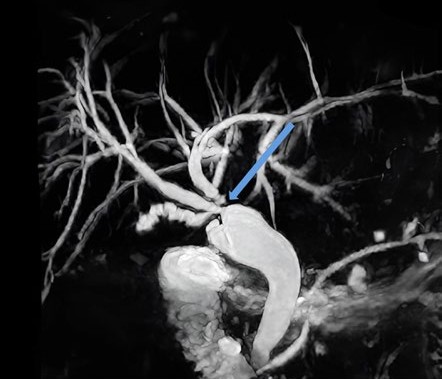

• Imaging “Mini-Atlas” of Vascular Liver Diseases

Rita Trovisco, Prof. Manuela França

48-59

DOI: https://doi.org/10.60591/crspmi.560